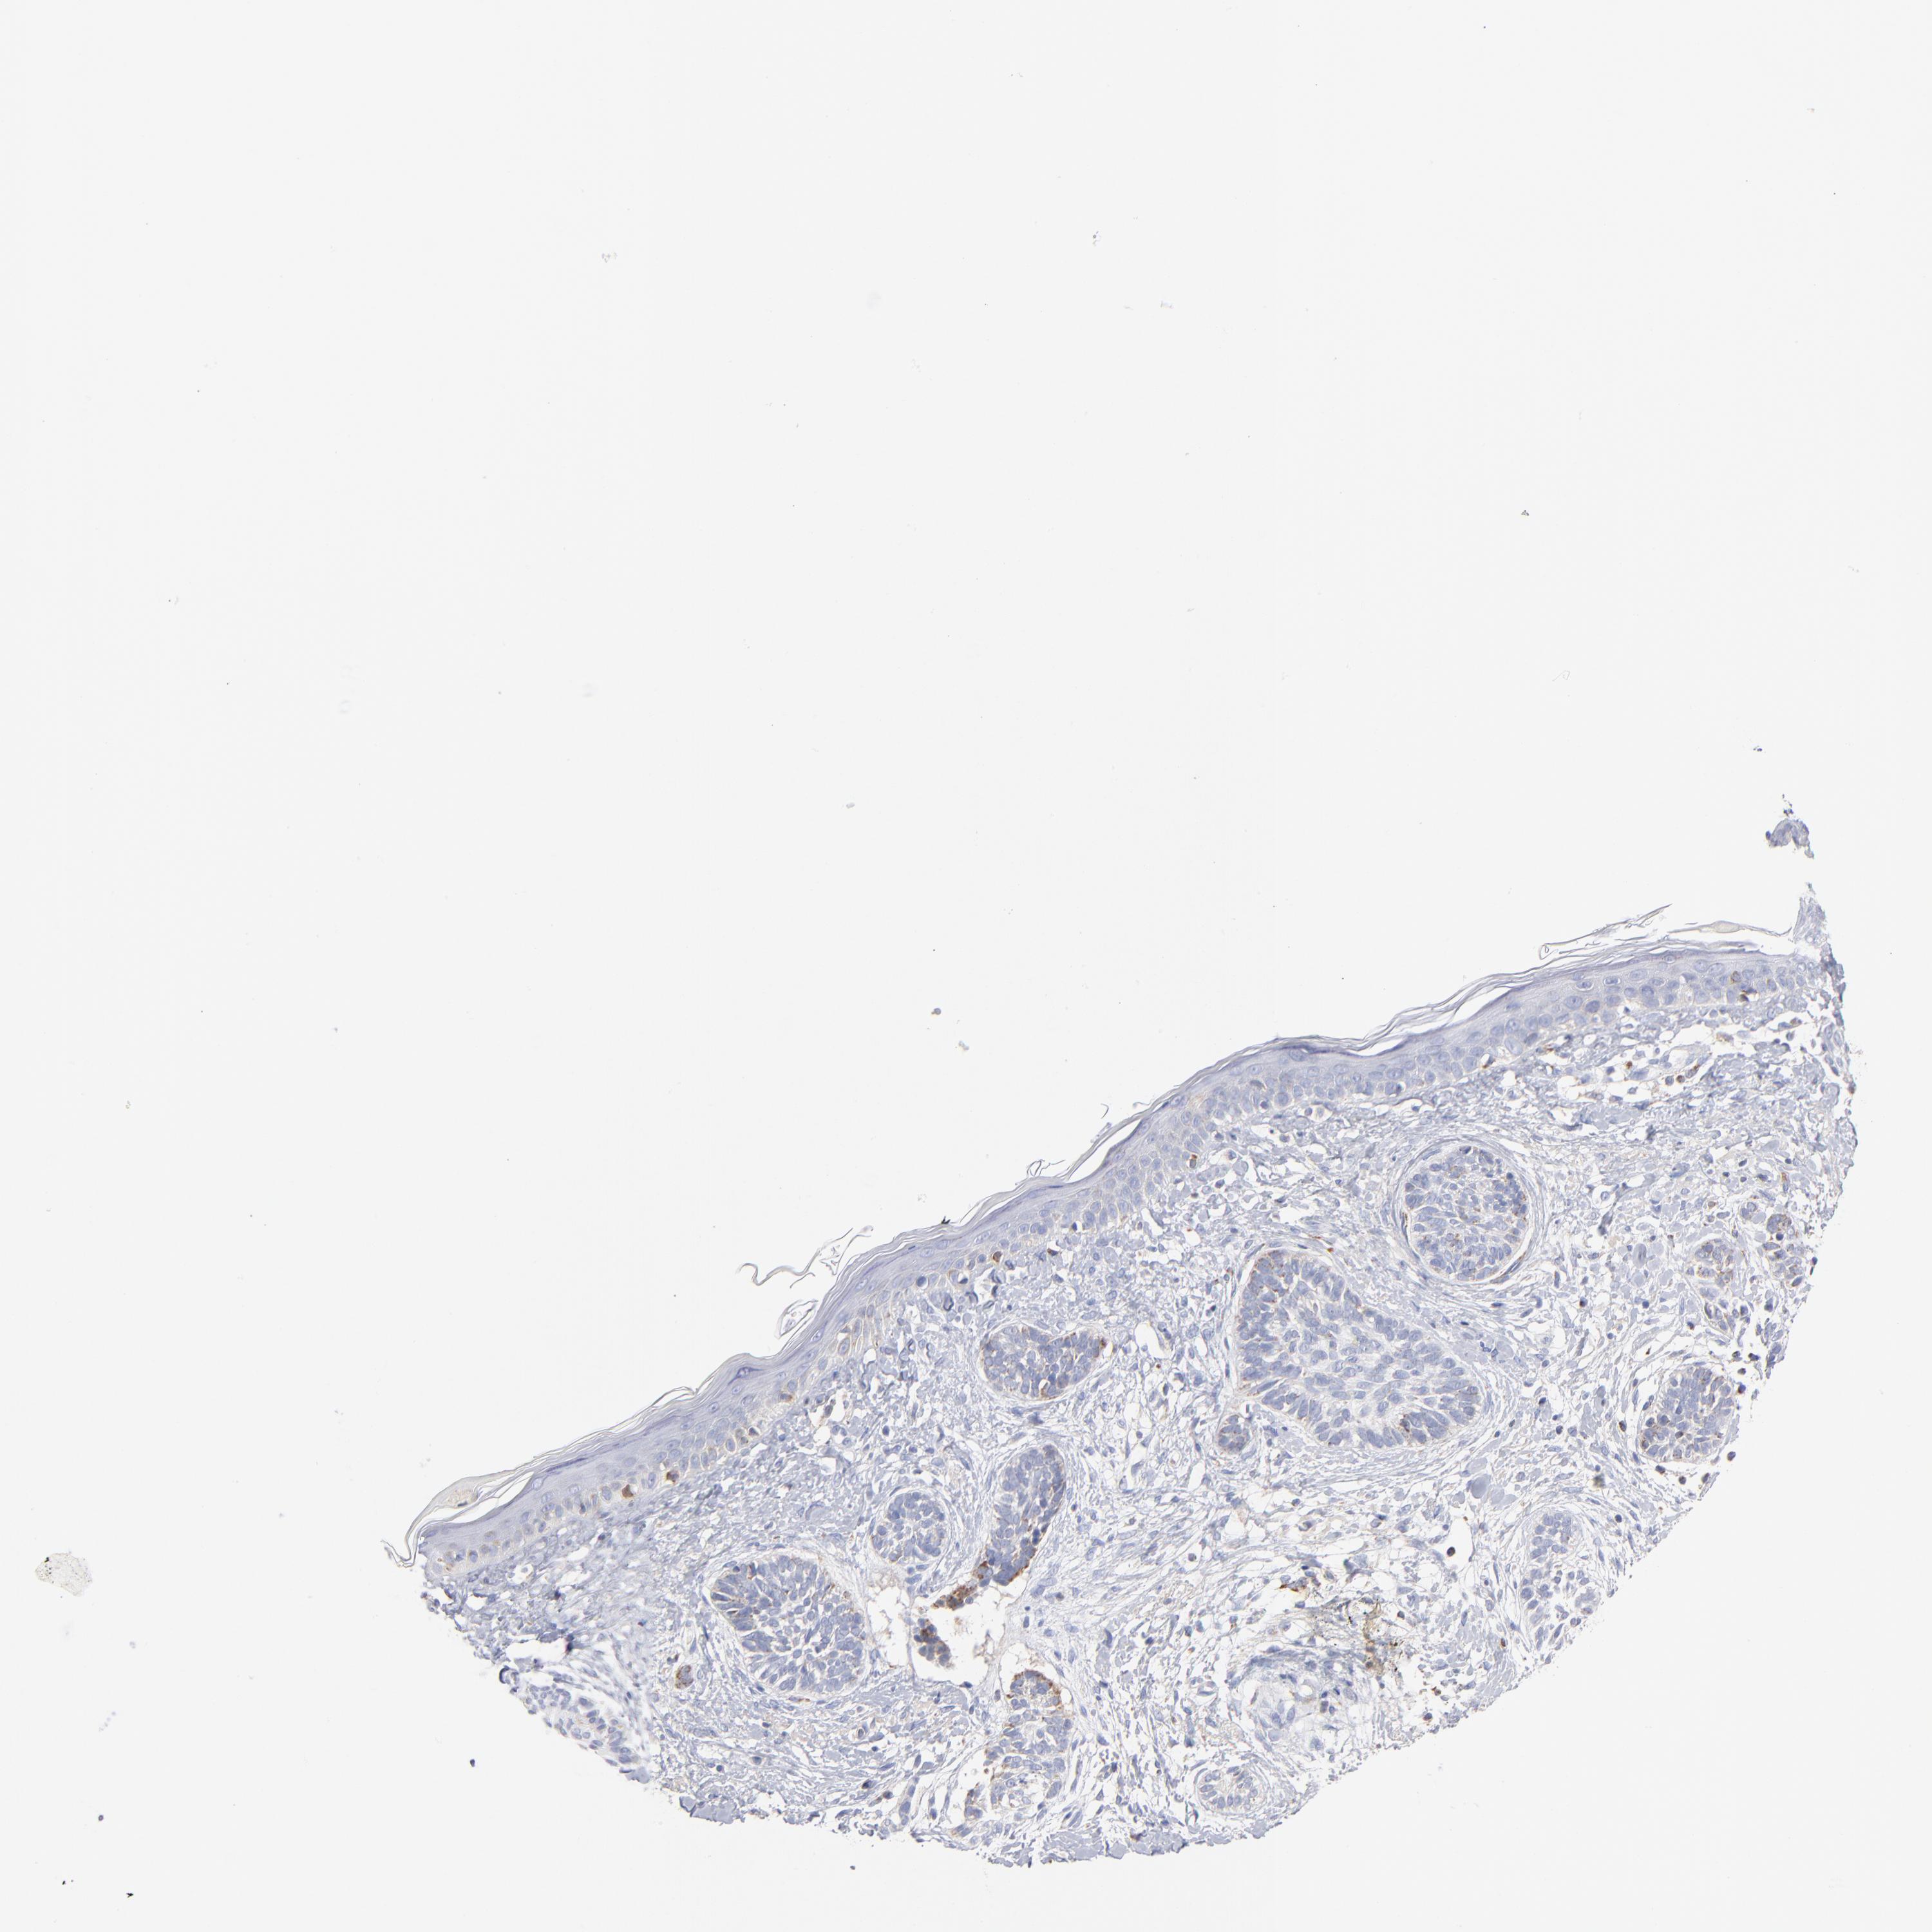

Basal cell and squamous cell cancer

SKIN CANCER - Protein expressioni

A mouse-over function shows sample information and annotation data. Click on an image to view it in a full screen mode. Samples can be filtered based on level of antibody staining by selecting one or several of the following categories: high, medium, low and not detected. The assay and annotation is described here.

Each image is clickable and will lead to virtual microscopy that enables deeper exploration of all samples and also displays staining intensity scores, fraction scores and subcellular localization as well as patient and tissue information for each sample.

Antibody HPA040786

Antibody CAB003782

Squamous cell carcinoma, NOS

Squamous cell carcinoma, metastatic, NOS

Basal cell carcinoma